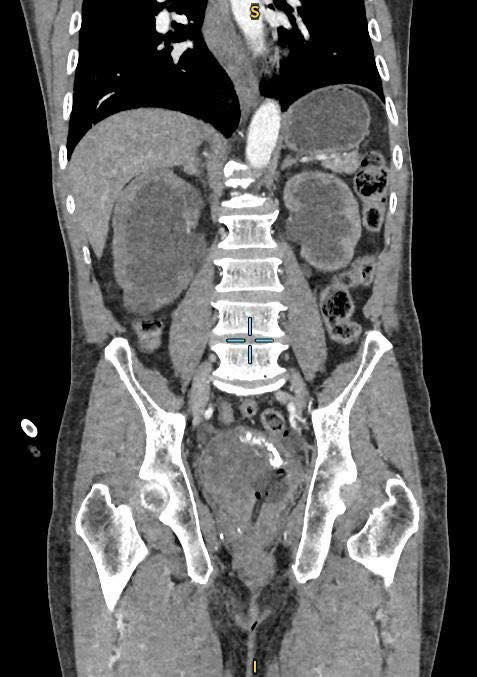

Tại đây, các bác sĩ khoa Ngoại Tiết Niệu đã thực hiện các cận lâm sàng chẩn đoán, ghi nhận người bệnh có bướu bàng quang to, khối u đã xâm lấn và chèn ép hai niệu quản gây thận ứ nước độ III, kèm suy thận. Ông N. được đặt ống sonde tiểu, hút ra một túi nước tiểu màu máu đỏ sậm.

Hình ảnh CT phát hiện bướu bàng quang và thận ứ nước - Ảnh BVCC